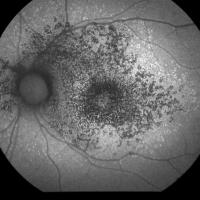

Fundus photograph of age-related macular degeneration showing drusen.

New research offers hope for preventing age-related blindness

New research from the University of Rochester provides important insights into the cellular mechanisms behind AMD and offers potential avenues for new treatments.